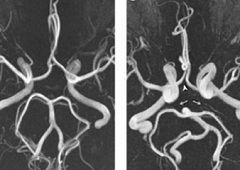

При гипоплазии сосудов Виллизиева круга симптомы могут отсутствовать, естественно при условии нормального кровотока в бассейнах других мозговых артерий. В этом случае патология выявляется как случайная диагностическая находка при проведении магниторезонансной томографии.

При проведении окулистом был поставлен диагноз: Гиперметропия слабой степени, нисходящая частичная атрофия зрительного нерва.. При проведении серии МР ангиограмм, выполненных в режиме TOF в аксиальной проекции с последующей обработкой выявлено следующее: внутренние сонные артерии имеют нормальный диаметр, расположены симметрично. Сифоны ВСА выражены отчетливо, без признаков компрессии. Отмечается извитость хода обеих ВСА.

Средние мозговые артерии и передние мозговые артерии отходят с каждой стороны от ВСА, не изменены.

Вариант развития Виллизиева круга в виде отсутствия кровотока по обеим задним соединительным артериям.

Основная артерия имеет обычный ход и диаметр и разделяется на задние мозговые артерии, которые имеют обычный диаметр.

Определяется сужение просвета и снижение кровотока по интракраниальному отделу правой ПА.